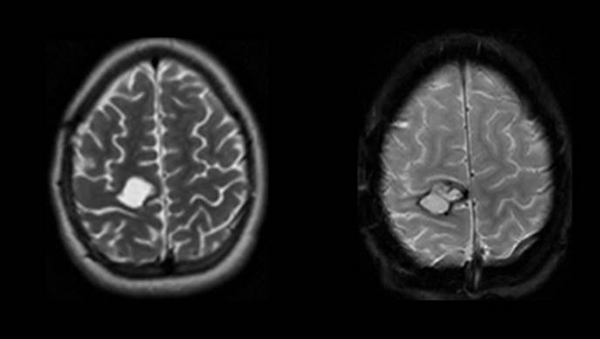

Se presenta un paciente femenino de 10 años que ingresa a nuestro hospital por presentar hemiparesia braquiocrural izquierda, vómitos y cefalea de 72 horas de evolución. Se constatan ambas papilas opticas sobreelevadas en el fondo de ojos. Se decide realizar tomografia computada (TC) (fig. 1) y resonania magnética nuclear (RMN) de encéfalo (fig. 2).

Figura 2: RM. A) corte axial; B) corte sagital; ambos ponderados en secuencia T1. Se aprecian bordes bien definidos, iso a hiperintenso, respecto del parénquima. El contenido se observa predominante iso a hipointenso con formación redondeada excéntrica de intensidad heterogénea. C) corte axial; D) corte coronal; ambos ponderados en secuencia T2. Se observa el contenido predominantemente hiperintenso de la lesión con la formación redondeada excéntrica rodeada de estructuras trabeculares y tabiques. Halo hiperintenso perilesional que se corresponde con edema.

Figura 8: RMN. A) Corte axial ponderado en T2. Se observa imagen redondeada en topografía del área precentral derecha compatible con lodge quirúrgica conteniendo LCR. B) Corte axial ponderado en GRE. Se observa halo hipointenso correspondiente a restos de hemosiderina.